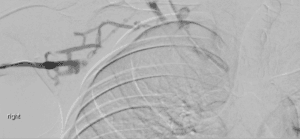

Vascular surgery was consulted and the patient underwent localized thrombolysis, thrombectomy and stent placement in the left iliac vein. The patient tolerated the procedure and did not have any complications. His symptoms, including fatigue and anorexia, gradually resolved. CRP concentrations declined to 115.4 mg/L, and the patient was discharged on post-op day 3 on Aspirin, Clopidogrel, and Apixaban with vascular surgery follow-up and age-appropriate cancer screening including colonoscopy. Of note, CT of the chest, abdomen, and pelvis did not reveal any evidence of malignancy, and prostatic-specific antigen (PSA) concentration was unremarkable. Thrombophilia work-up was not indicated given the patient’s age, the absence of a history of thromboembolic episodes, and the detection of an anatomic risk factor for thrombosis, MTS.